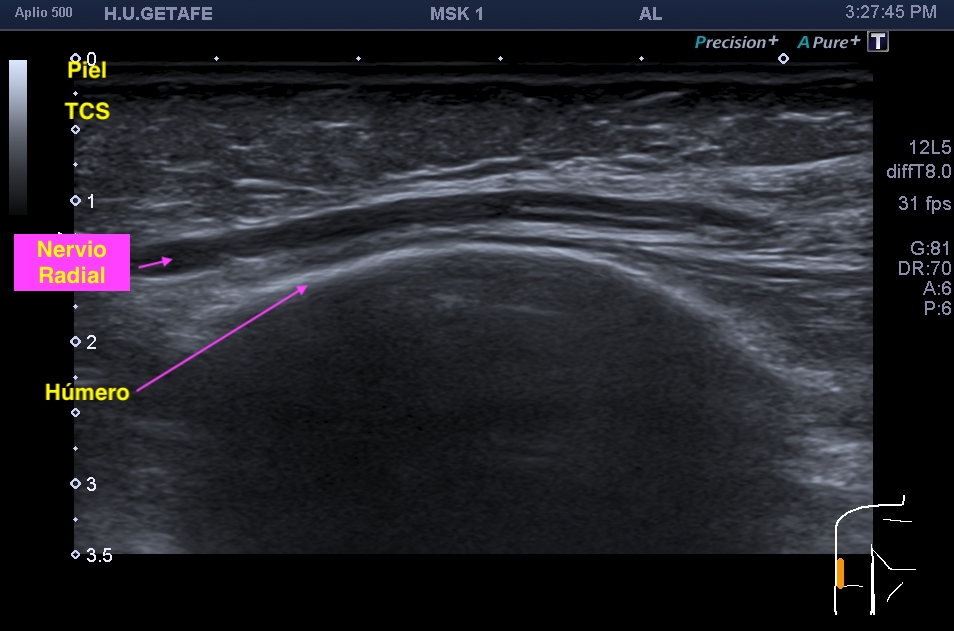

La radiografía revela aumento de las partes y se refrenda en la ecografía como puedes ver en la imagen aunque aún no hay afectación en el hueso en el caso que te presento hoy.

Ecografícamente y debido a su levedad, en el caso de hoy solo observamos cambios en las partes blandas de la cara lateral de la cabeza del quinto metatarsiano, este tejido se muestra heterogéneo, la cortical del hueso ligeramente prominente sin afectación de la misma.